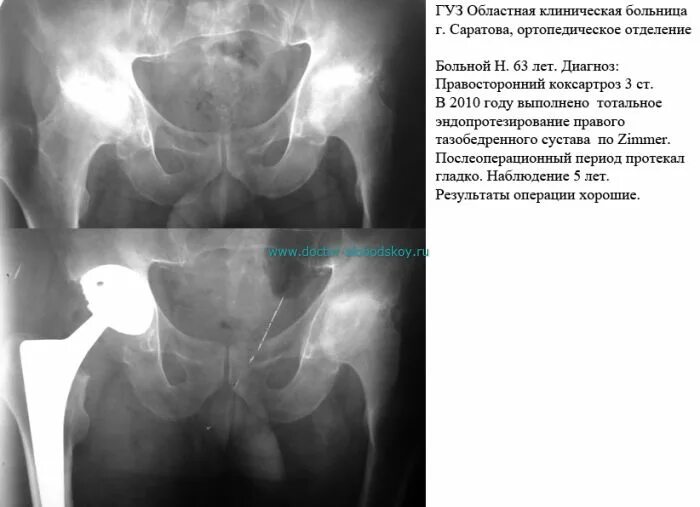

Коксартроз тазобедренного 3 степени операция